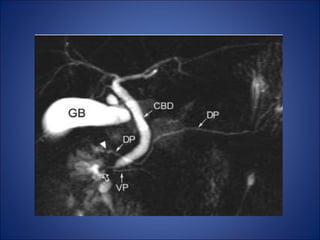

MRI Abdomen

• Adv to MSCT:

– Superior soft-tissue contrast

even without IV contrast.

– Assessing the morphologic

features of pancreatic cysts.

– MRCP provides excellent

depiction of the pancreatic duct

anatomy and biliary channel.

Pancreatic divisum

• The ventral bud failed to fuse

• The pancreatic head and

uncinate process are drained

through the major papilla.

• The body and tail of the

pancreas are drained through

the minor papilla.

• As a result ,the dorsal

pancreatic duct drains most of

the pancreas via the minor

papilla that may lead to

recurrent attack of pancreatitis

Annular Pancreas